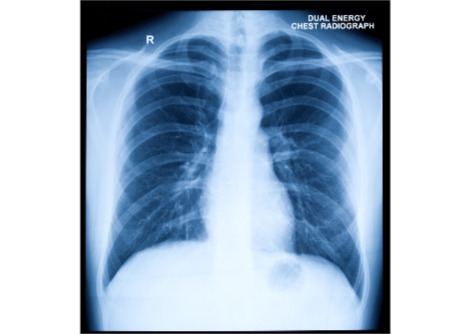

فحص البحث السجلات الصحية الإلكترونية التي امتدت على مدى 20 عامًا، من عام 2003 إلى عام 2023، وغطت أكثر من 407,000 بالغ سليم يتلقون الرعاية من خلال خدمات الرعاية الصحية "لئوميت"، أحد أبرز مقدمي الرعاية الصحية في إسرائيل. وتُعد هذه الدراسة واحدة من أكبر الدراسات وأكثرها تفصيلًا على الإطلاق لاستكشاف تأثير مستويات الترطيب على صحة القلب على المدى الطويل. وقد نُشرت النتائج مؤخرًا في المجلة الأوروبية لأمراض القلب الوقائية.

لطالما اعتُبر الصوديوم، الذي يُفحص عادةً في فحوصات الدم القياسية، طبيعيًا ضمن نطاق 135-146 مليمول/لتر. لكن هذه الدراسة تُشكك في هذا الافتراض، مُشيرةً إلى وجود ارتباط قوي وطويل الأمد بين ارتفاع مستويات الصوديوم وخطر الإصابة بأمراض القلب والأوعية الدموية، حتى بين من يُعتبرون أصحاء.

ظلت هذه الارتباطات قوية حتى بعد تعديل عوامل العمر والجنس ومؤشر كتلة الجسم وضغط الدم والتدخين ومستويات البوتاسيوم. استثنى التحليل الأفراد الذين يعانون من حالات تؤثر على توازن الماء في الجسم لضمان انعكاس أدق للمخاطر المتعلقة بالترطيب.